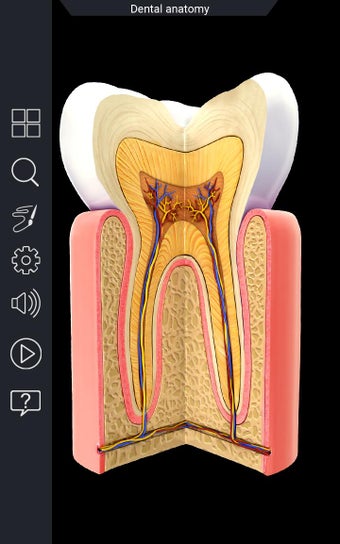

Esta aplicación es un modelo 3D de los dientes, que contiene muchas partes y muestra las condiciones dentales. Cada parte tiene un nombre y una función. Puedes mover la cámara alrededor del modelo para obtener una vista de 360° de las diferentes partes. Puedes hacer zoom para ver mejor cada parte. También puedes rotar la cámara para obtener una vista diferente del modelo.